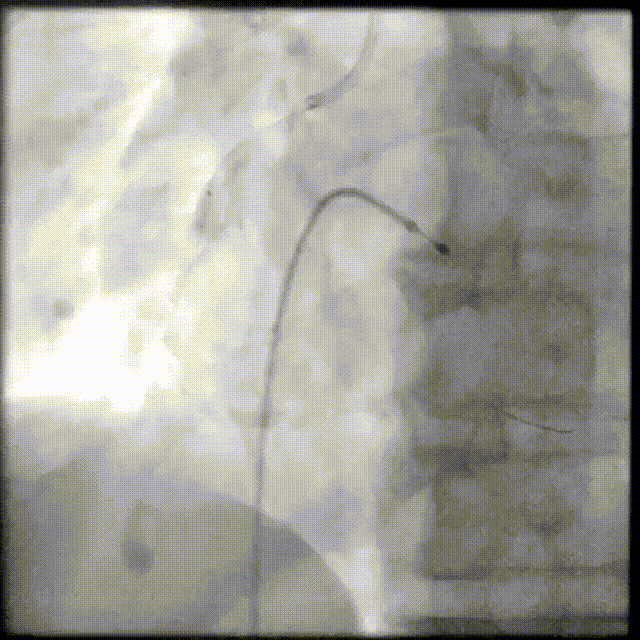

PCI过程-冲击波球囊PTCA

沿导丝送3.0×12mmGennWave冲击波球囊至RCA严重钙化病变处,充盈1:1比例造影剂盐水,以4atm低压扩张,每周期给予10秒、每秒1次血管内冲击波治疗后扩张至6atm,共进行8周期血管内冲击波治疗。